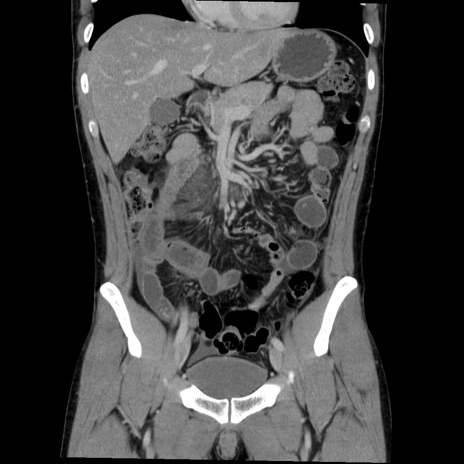

症例36(冠状断像)

【症例】20歳代 男性

【主訴】心窩部痛

【現病歴】今朝より上腹部痛あり。一旦軽快していたが再度出現したため救急要請。昨日夕に白身の魚を含む刺身を食べた。

【身体所見】BP 136/89mmHg、HR 74/min、BT 37.0℃、腹部:膨満、軟、心窩部に圧痛あり。反跳痛なし、筋性防御なし、腸雑音やや亢進あり。

【データ】WBC 17700、CRP 0.48